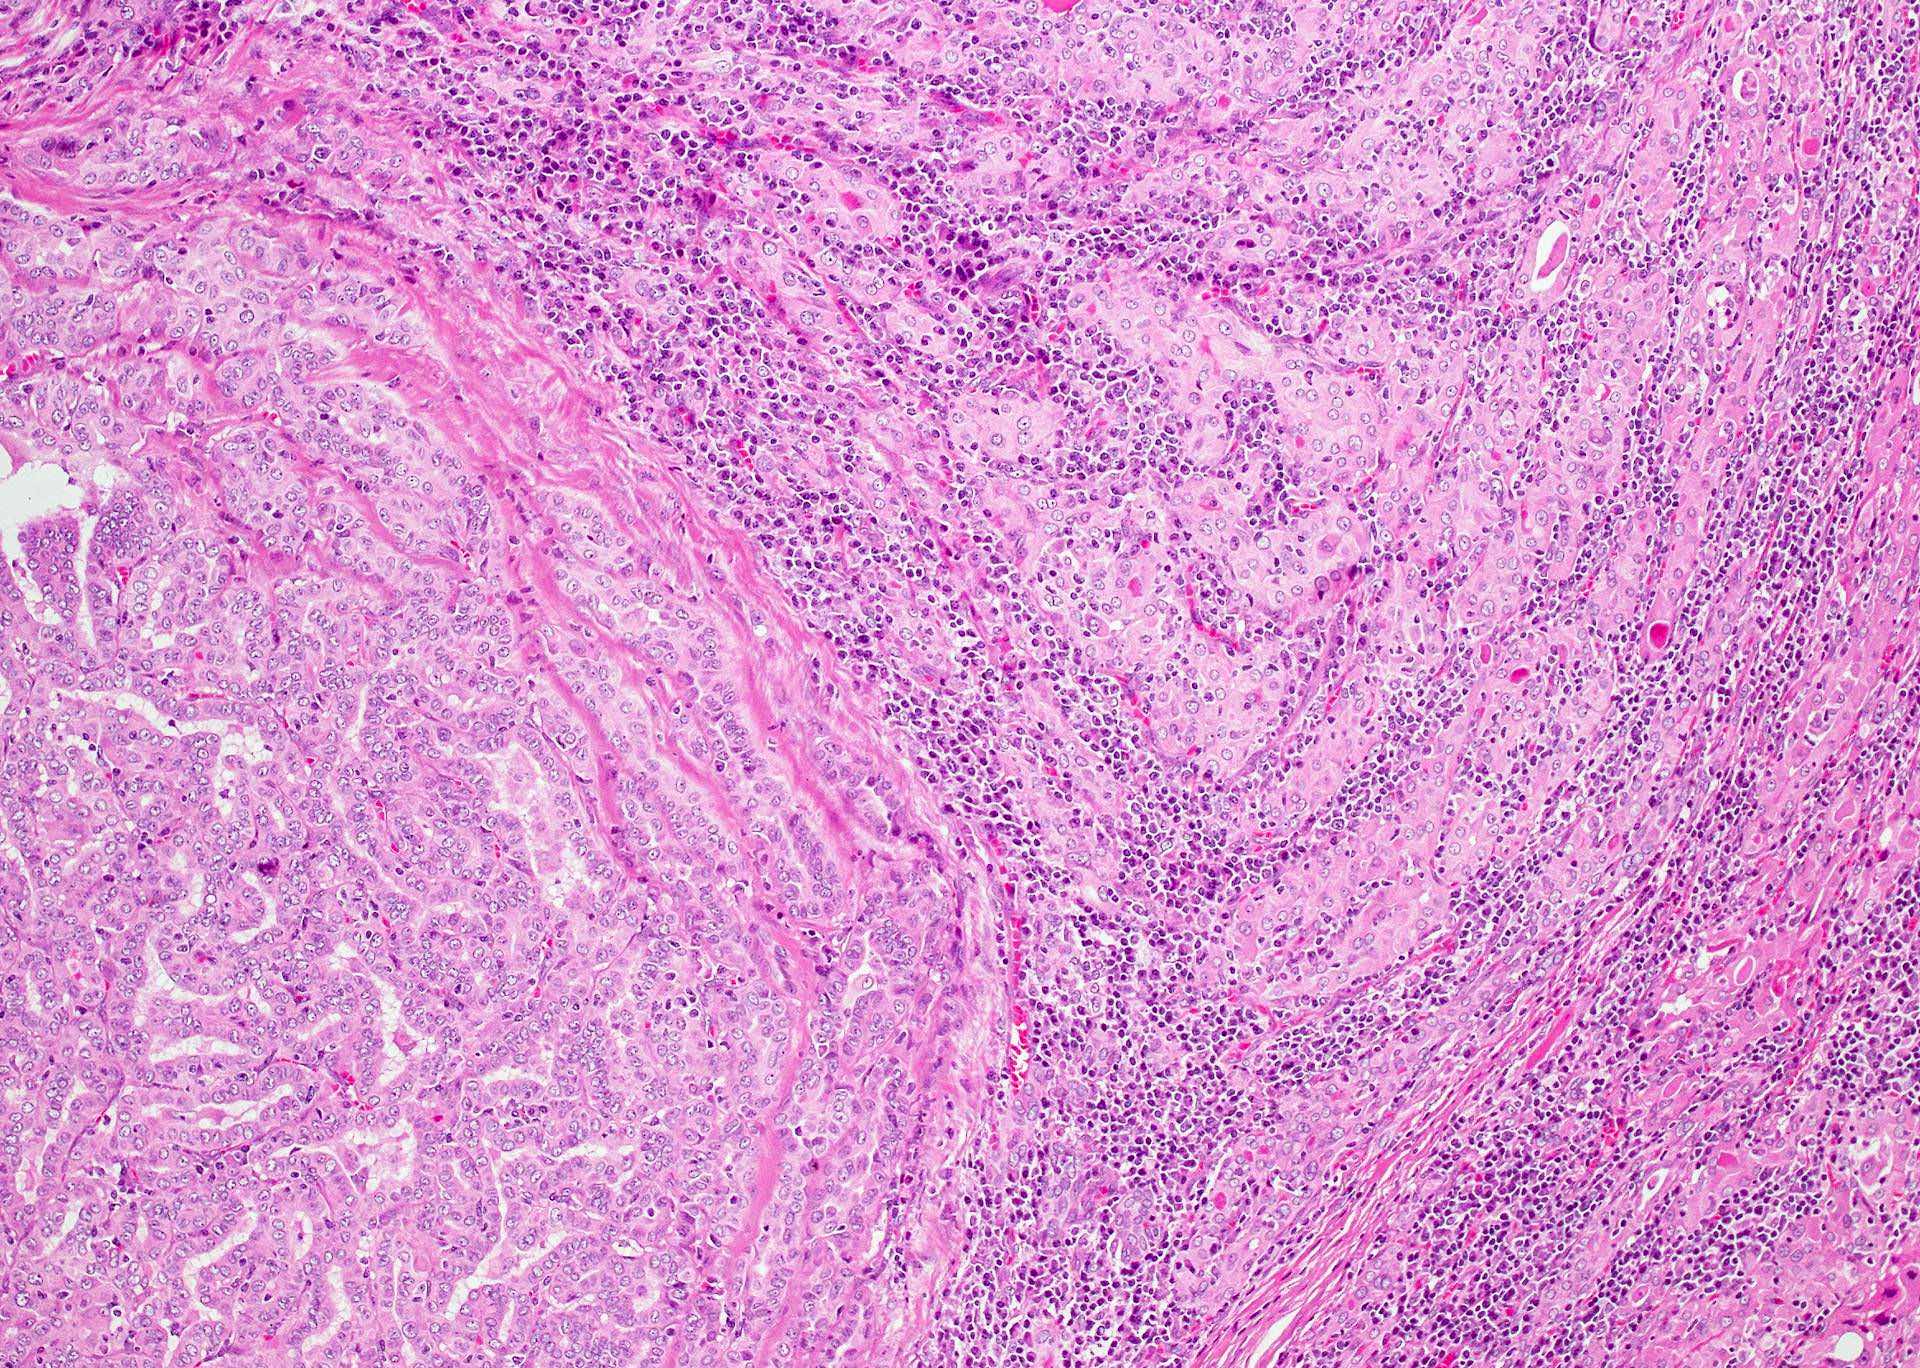

Microscopic (histologic) description

- Classic form: diffuse infiltration of thyroid parenchyma with lymphocytes and plasma cells; lymphoid follicle formation with germinal centers (Best Pract Res Clin Endocrinol Metab 2019;33:101367)

- Polymorphic lymphocytic infiltrate, predominantly T cells

- Thyroid follicular destruction

- Atrophic thyroid follicles; many lined by oncocytic cells / oncocytes having abundant granular eosinophilic cytoplasm; rarely squamous metaplasia

- Later fibrosis and nodularity (Virchows Arch 2013;462:557)

- Fibrous (or fibrosing) variant: extensive keloid-like fibrosis of thyroid parenchyma, fibrous septa divide the parenchyma into lobules, mononuclear cell infiltration, lymphoid follicles, thyroid follicular atrophy, oncocytic cell and squamous metaplasia (Autoimmun Rev 2014;13:391)

- IgG4 related variant: dense lymphoplasmacytic infiltrate, enriched in IgG4 producing plasma cells (> 20 cells per high power field); interstitial fibrosis; often associated with obliterative phlebitis (Autoimmun Rev 2014;13:391)

- Variable atypia of follicular cells and oncocytic cells, may mimic and act as a precursor (limited evidence) of papillary thyroid carcinoma (Endocr Pathol 2021;32:368)

- Squamous metaplasia of follicular epithelium can be confused with solid cell nests (J Clin Endocrinol Metab 2012;97:2209)

Microscopic (histologic) images

Contributed by Andrey Bychkov, M.D., Ph.D. and Shipra Agarwal, M.D.